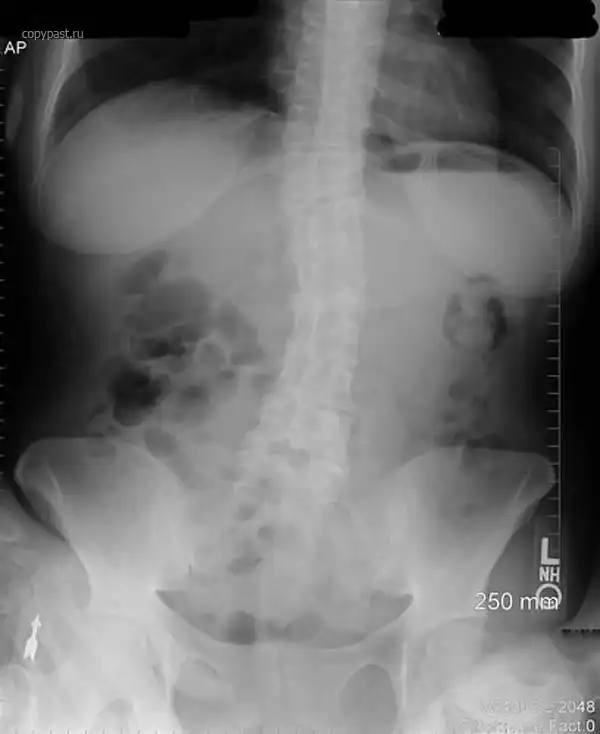

Человек проглотил зубную щетку. Справа в верхней части видна ее головка